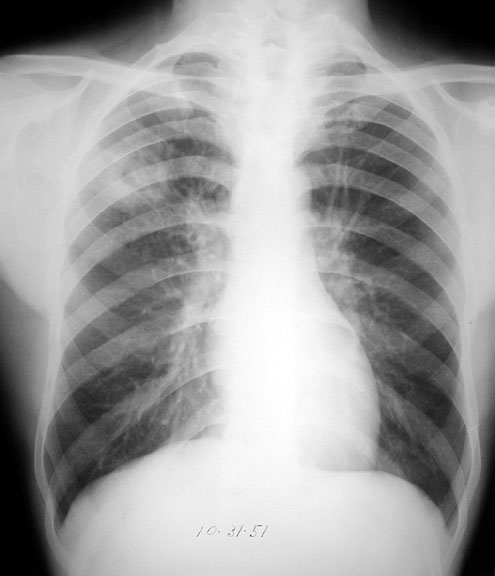

Tuberculosis

• RUL cavity

• Posterior segment

Close up below.